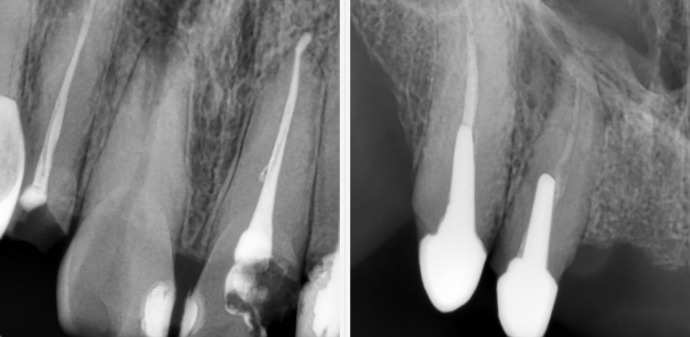

Ни в коем случае не пренебрегайте рентгенологическим обследованием. Первичные точные снимки конкретных зубов проводятся для более точной диагностики. Во время лечения также проводится промежуточная рентгенология — для соблюдения контроля, но самый главный снимок осуществляется уже по заключению процедуры лечения.

Визиограмма оцифровывается и переводится на персональный компьютер, после чего может быть мгновенно передана в любую точку мира по интернету, через Wi-Fi, или Bluetooth на ваше мобильное устройство или на флешку. Вы можете просматривать и десятикратно увеличивать каждый отдельный фрагмент изображения как отдельной рентгенограммы. Цифровая визиограмма может быть редактирована и оптимизирована для лучшего визуального восприятия с добавлением различных фильтров в фотошопе, после чего распечатана неограниченное кол-во раз.

Также визиограф раскрывает ту часть зуба, которая физически не видна стоматологу, что позволяет установить диагноз в более точных подробностях.

Напоминаем вам! Именно по рентгенографическим снимкам специалист может скорректировать свою работу, оценить качество пломбирования каналов, избежать появления вероятных осложнений и отследить весь процесс своей деятельности поэтапно.